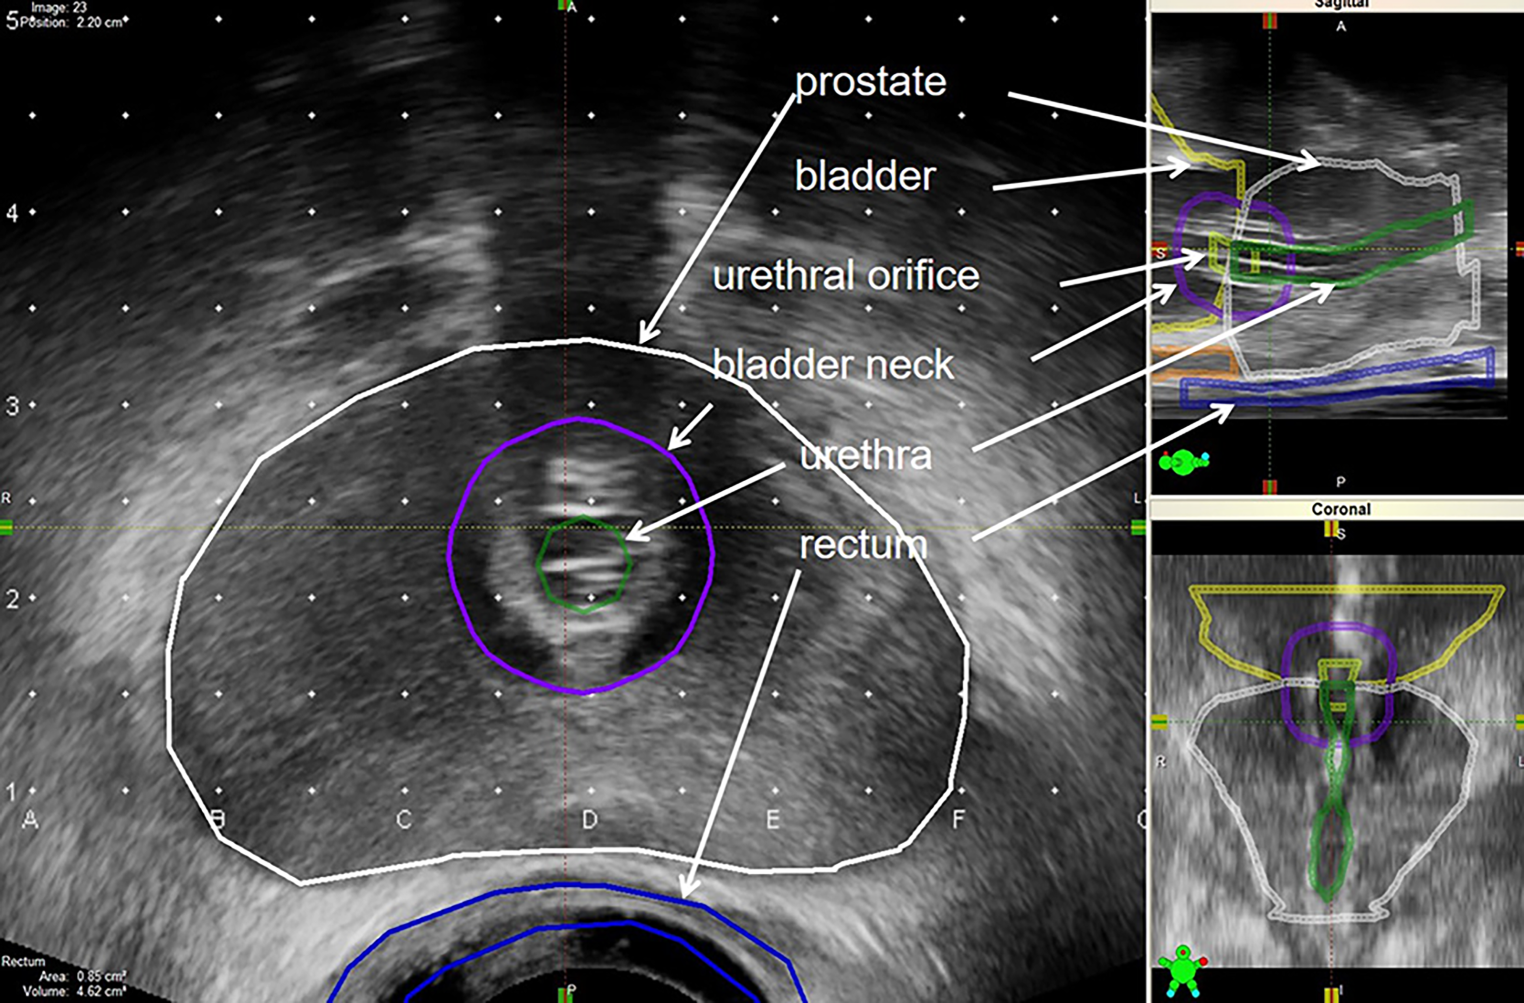

Nadat de patiënt onder narcose was gebracht en in steensnede was gepositioneerd, werd ten behoeve van de implantatieplanning een serie transrectale echobeelden van de prostaat gemaakt. Gedurende de periode 2002–2023 werd gebruikgemaakt van het Variseed-planningsysteem van Varian (versies 6,7 tot en met 9,02). Het opnemen van echobeelden gebeurde aanvankelijk door de transrectale echoprobe met de stepper telkens 5 mm te verplaatsen vanaf ongeveer 20 mm craniaal van de basis tot circa 10 mm voorbij de apex, en de achtereenvolgende transversale beelden in Variseed te importeren. De stepper is een statief waar de echoprobe in geklemd wordt, en vervolgens in craniaal-caudale richting getransleerd en om de lengteas geroteerd kan worden. Met de ingebruikname van een zogenaamde tracked stepper (Civco) in combinatie met de FlexFocus-echograaf van BK in respectievelijk 2011 en 2012 konden er om de mm transversale echobeelden worden gemaakt, waardoor er een betere 3D-reconstructie kon worden gerealiseerd (zie fig. 1). De zaadstrengen werden volgens het implantatieplan geassembleerd en in implantienaalden ingevoerd, om vervolgens onder echogeleide via het perineum in de prostaat te worden geïmplanteerd (zie fig. 2).

Figuur 1

Opgenomen transrectale echobeelden met een tracked stepper. Links het opgenomen transversale beeld, rechts het gereconstrueerde sagittale en coronale beeld. Voor andere vlakken kon met de muis door de beelden worden gescrold. De verschillende structuren werden ingetekend om dosis-volumehistogrammen te kunnen bepalen